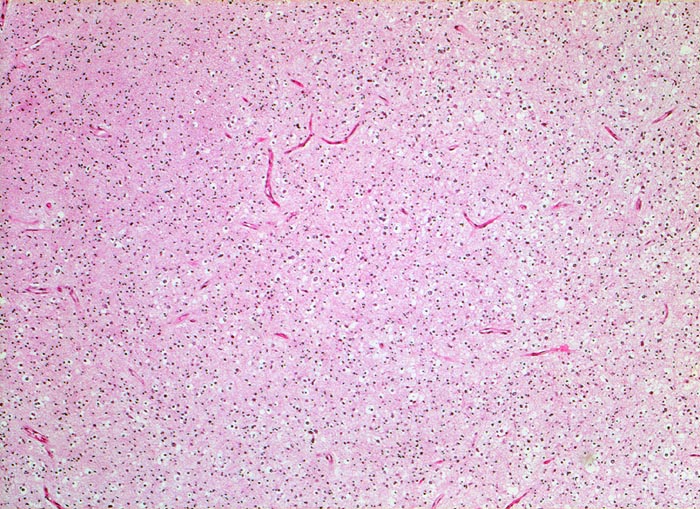

PathoPic – image database / PathoPic ID 5263 - Oligodendrogliom (WHO Grad II)

Oligodendrogliom (WHO Grad II)

Hirn frontal

Die von einem Halo umgebenen Tumorzellen erinnern bei schwacher Vergrösserung an Oligodendrozyten der weissen Substanz. Zahlreiche verzweigte Kapillaren.

Kopfschmerzen und epileptische Anfälle seit zwei Jahren.

Histologie

Vergrösserung